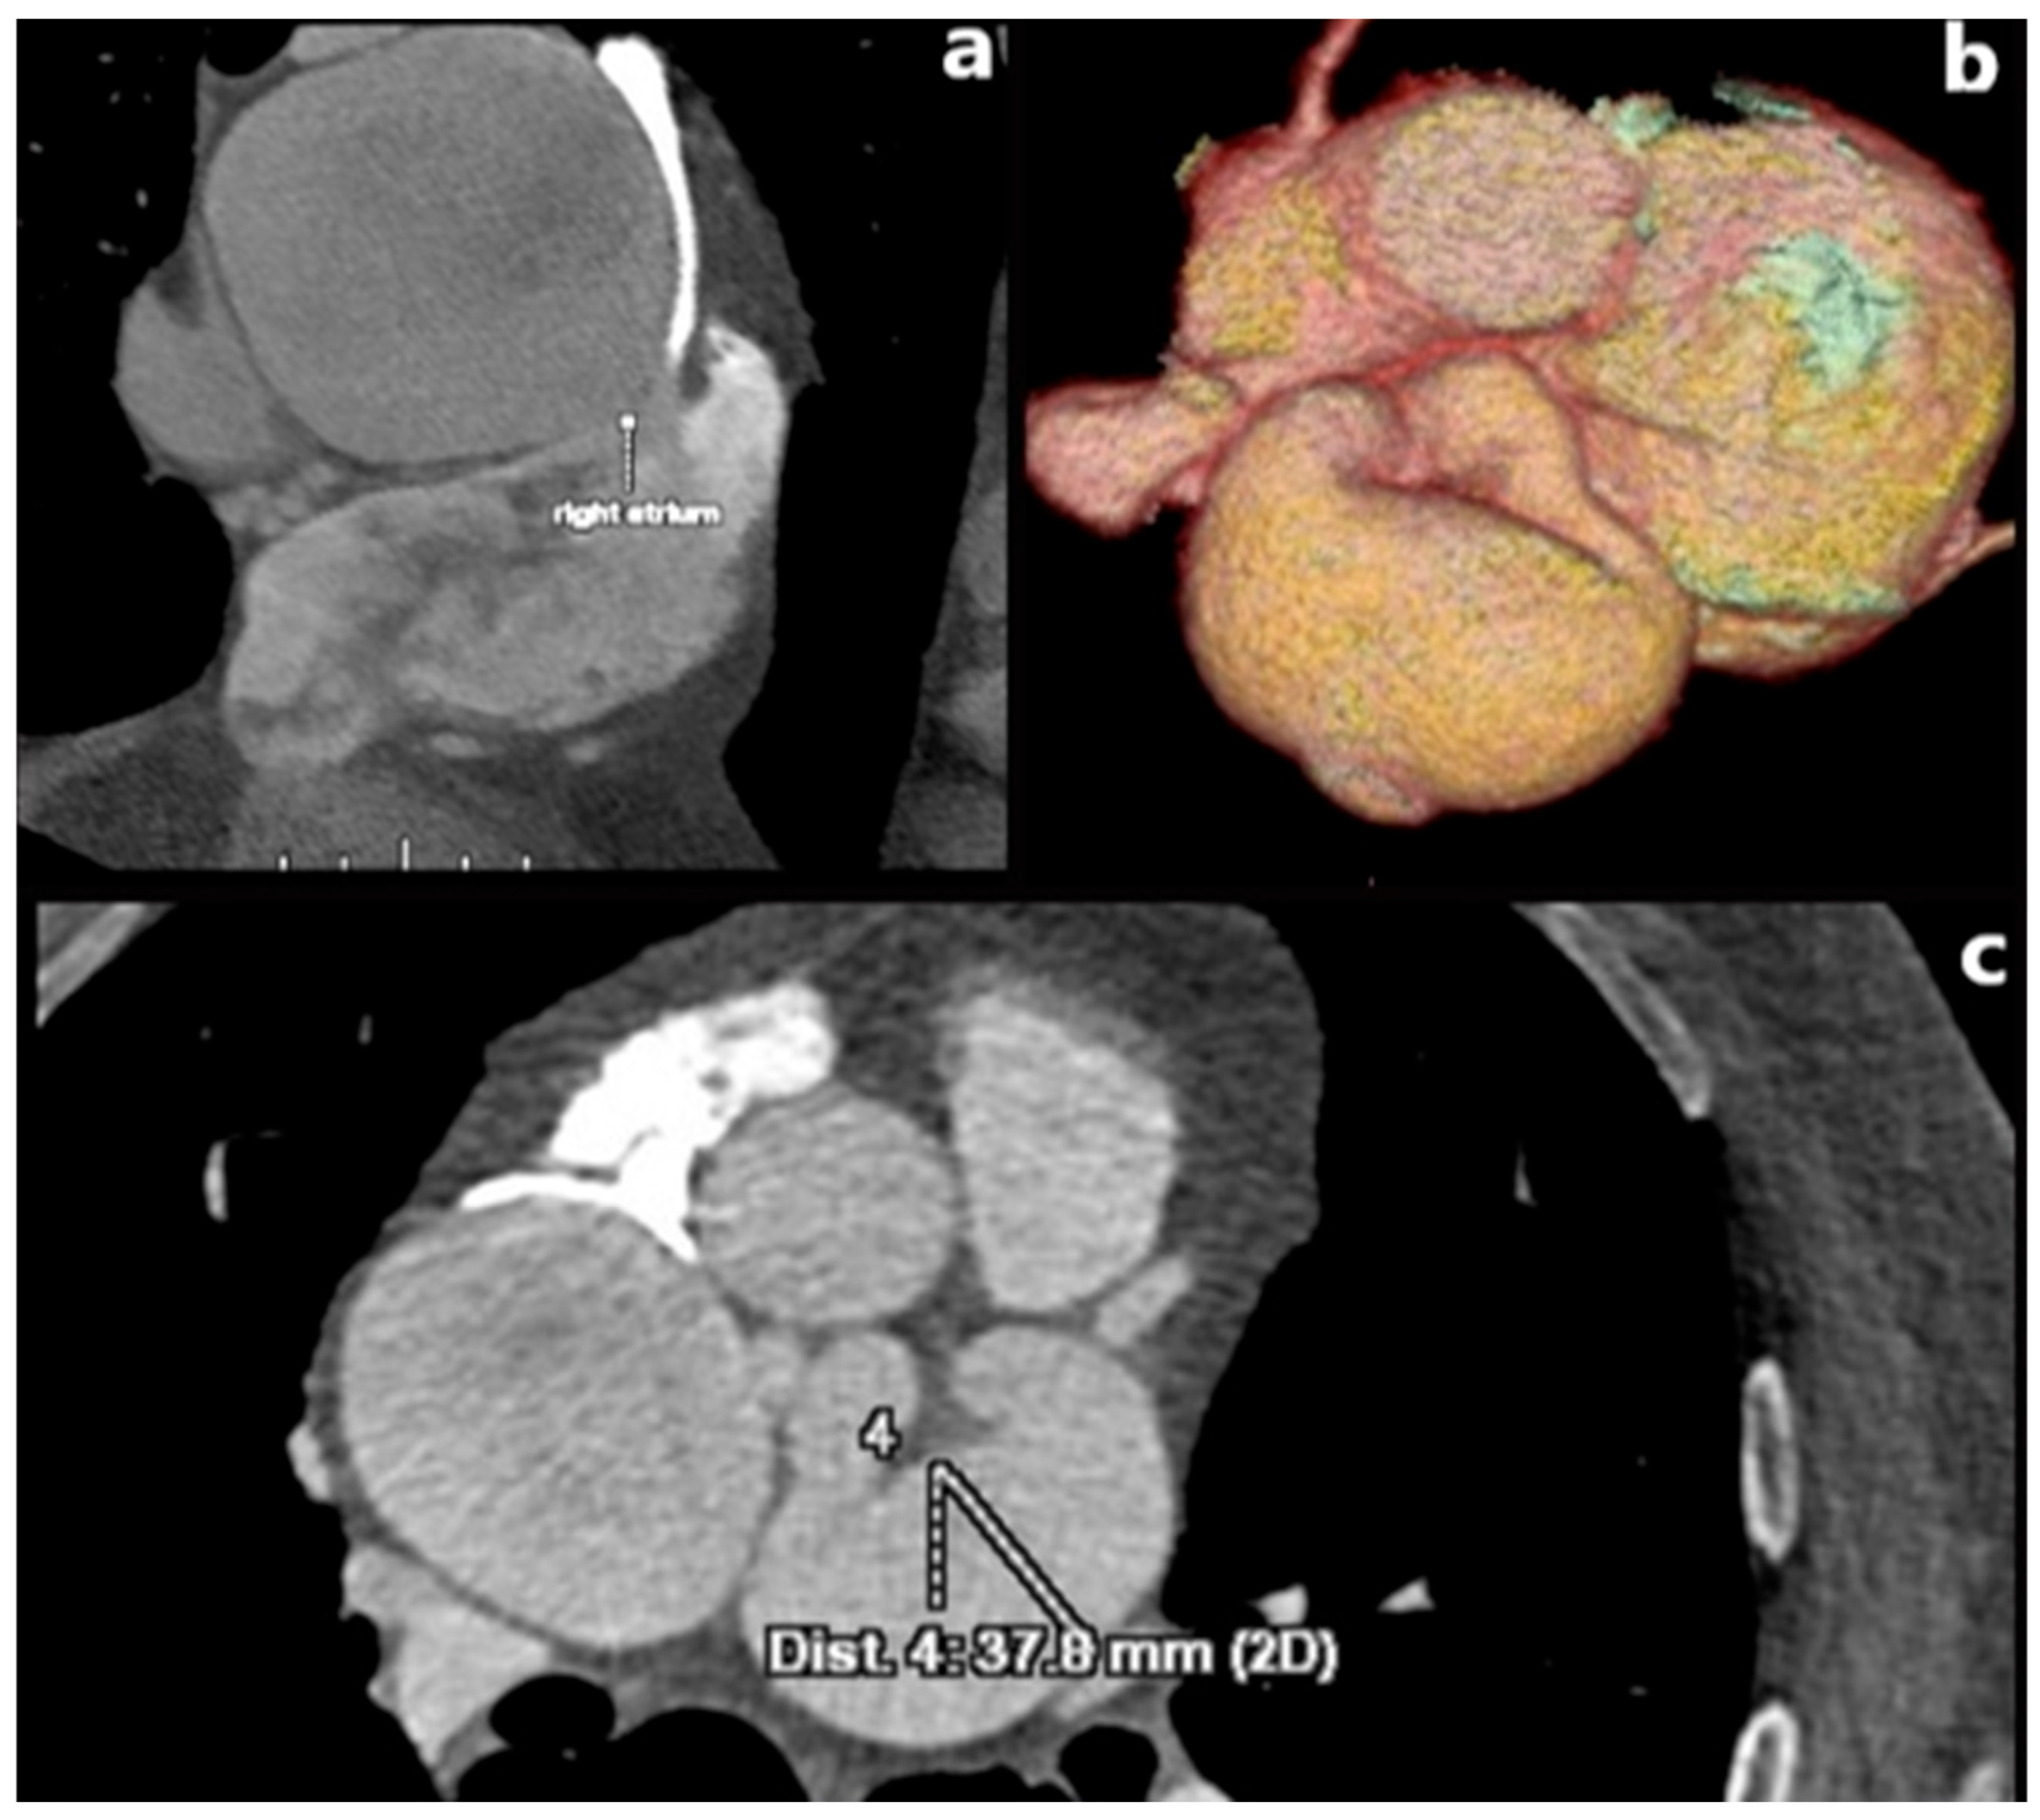

3.5. Coronary Artery Dissection

Aortic Dissection with Extension into the Coronary Arteries